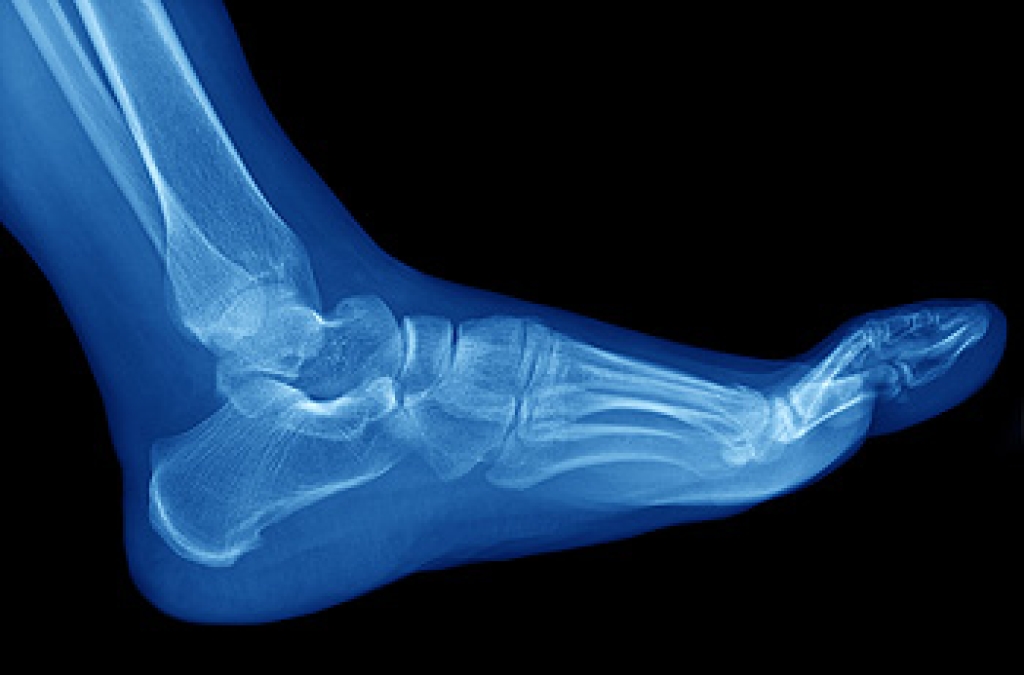

To figure out the cause of foot pain, podiatrists utilize several different methods. This can range from simple visual inspections and sensation tests to X-rays and MRI scans. Prior medical history, family medical history, and any recent physical traumatic events will all be taken into consideration for a proper diagnosis.